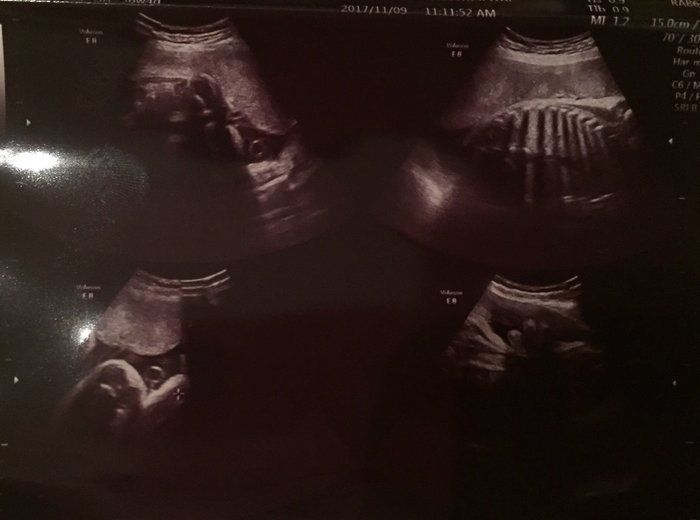

2人目が初男の子。写ったシンボルにびっくり。エコー写真で振り返る妊婦生活 -